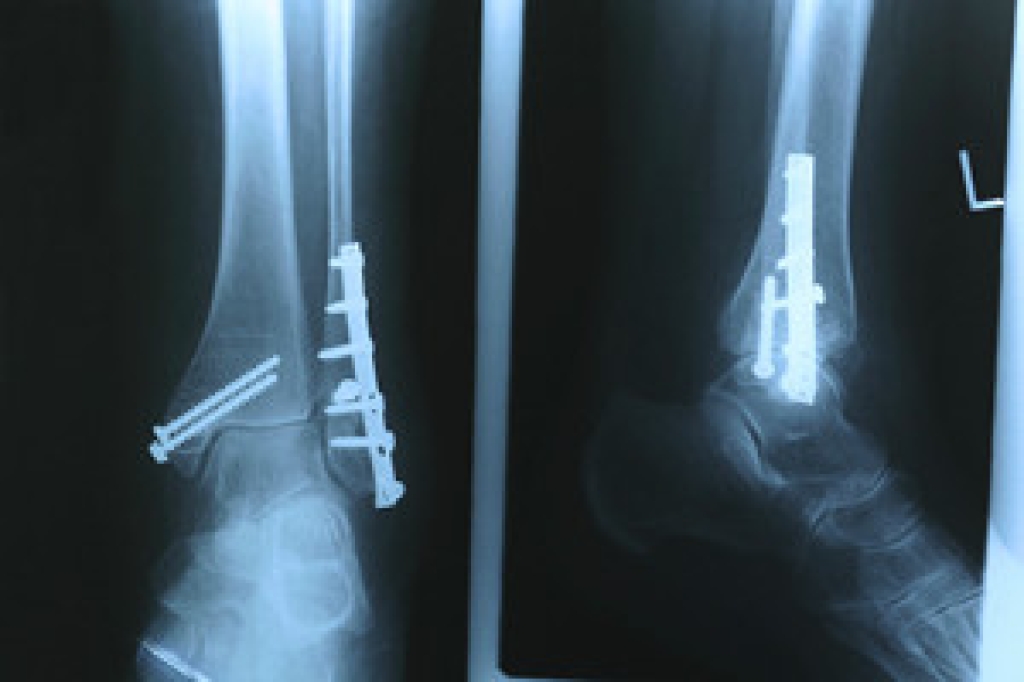

Diagnosis of cuboid syndrome is often difficult, and it is often misdiagnosed. X-rays, MRIs and CT scans often fail to properly show the cuboid subluxation. Although there isn’t a specific test used to diagnose cuboid syndrome, your podiatrist will usually check if pain is felt while pressing firmly on the cuboid bone of your foot.